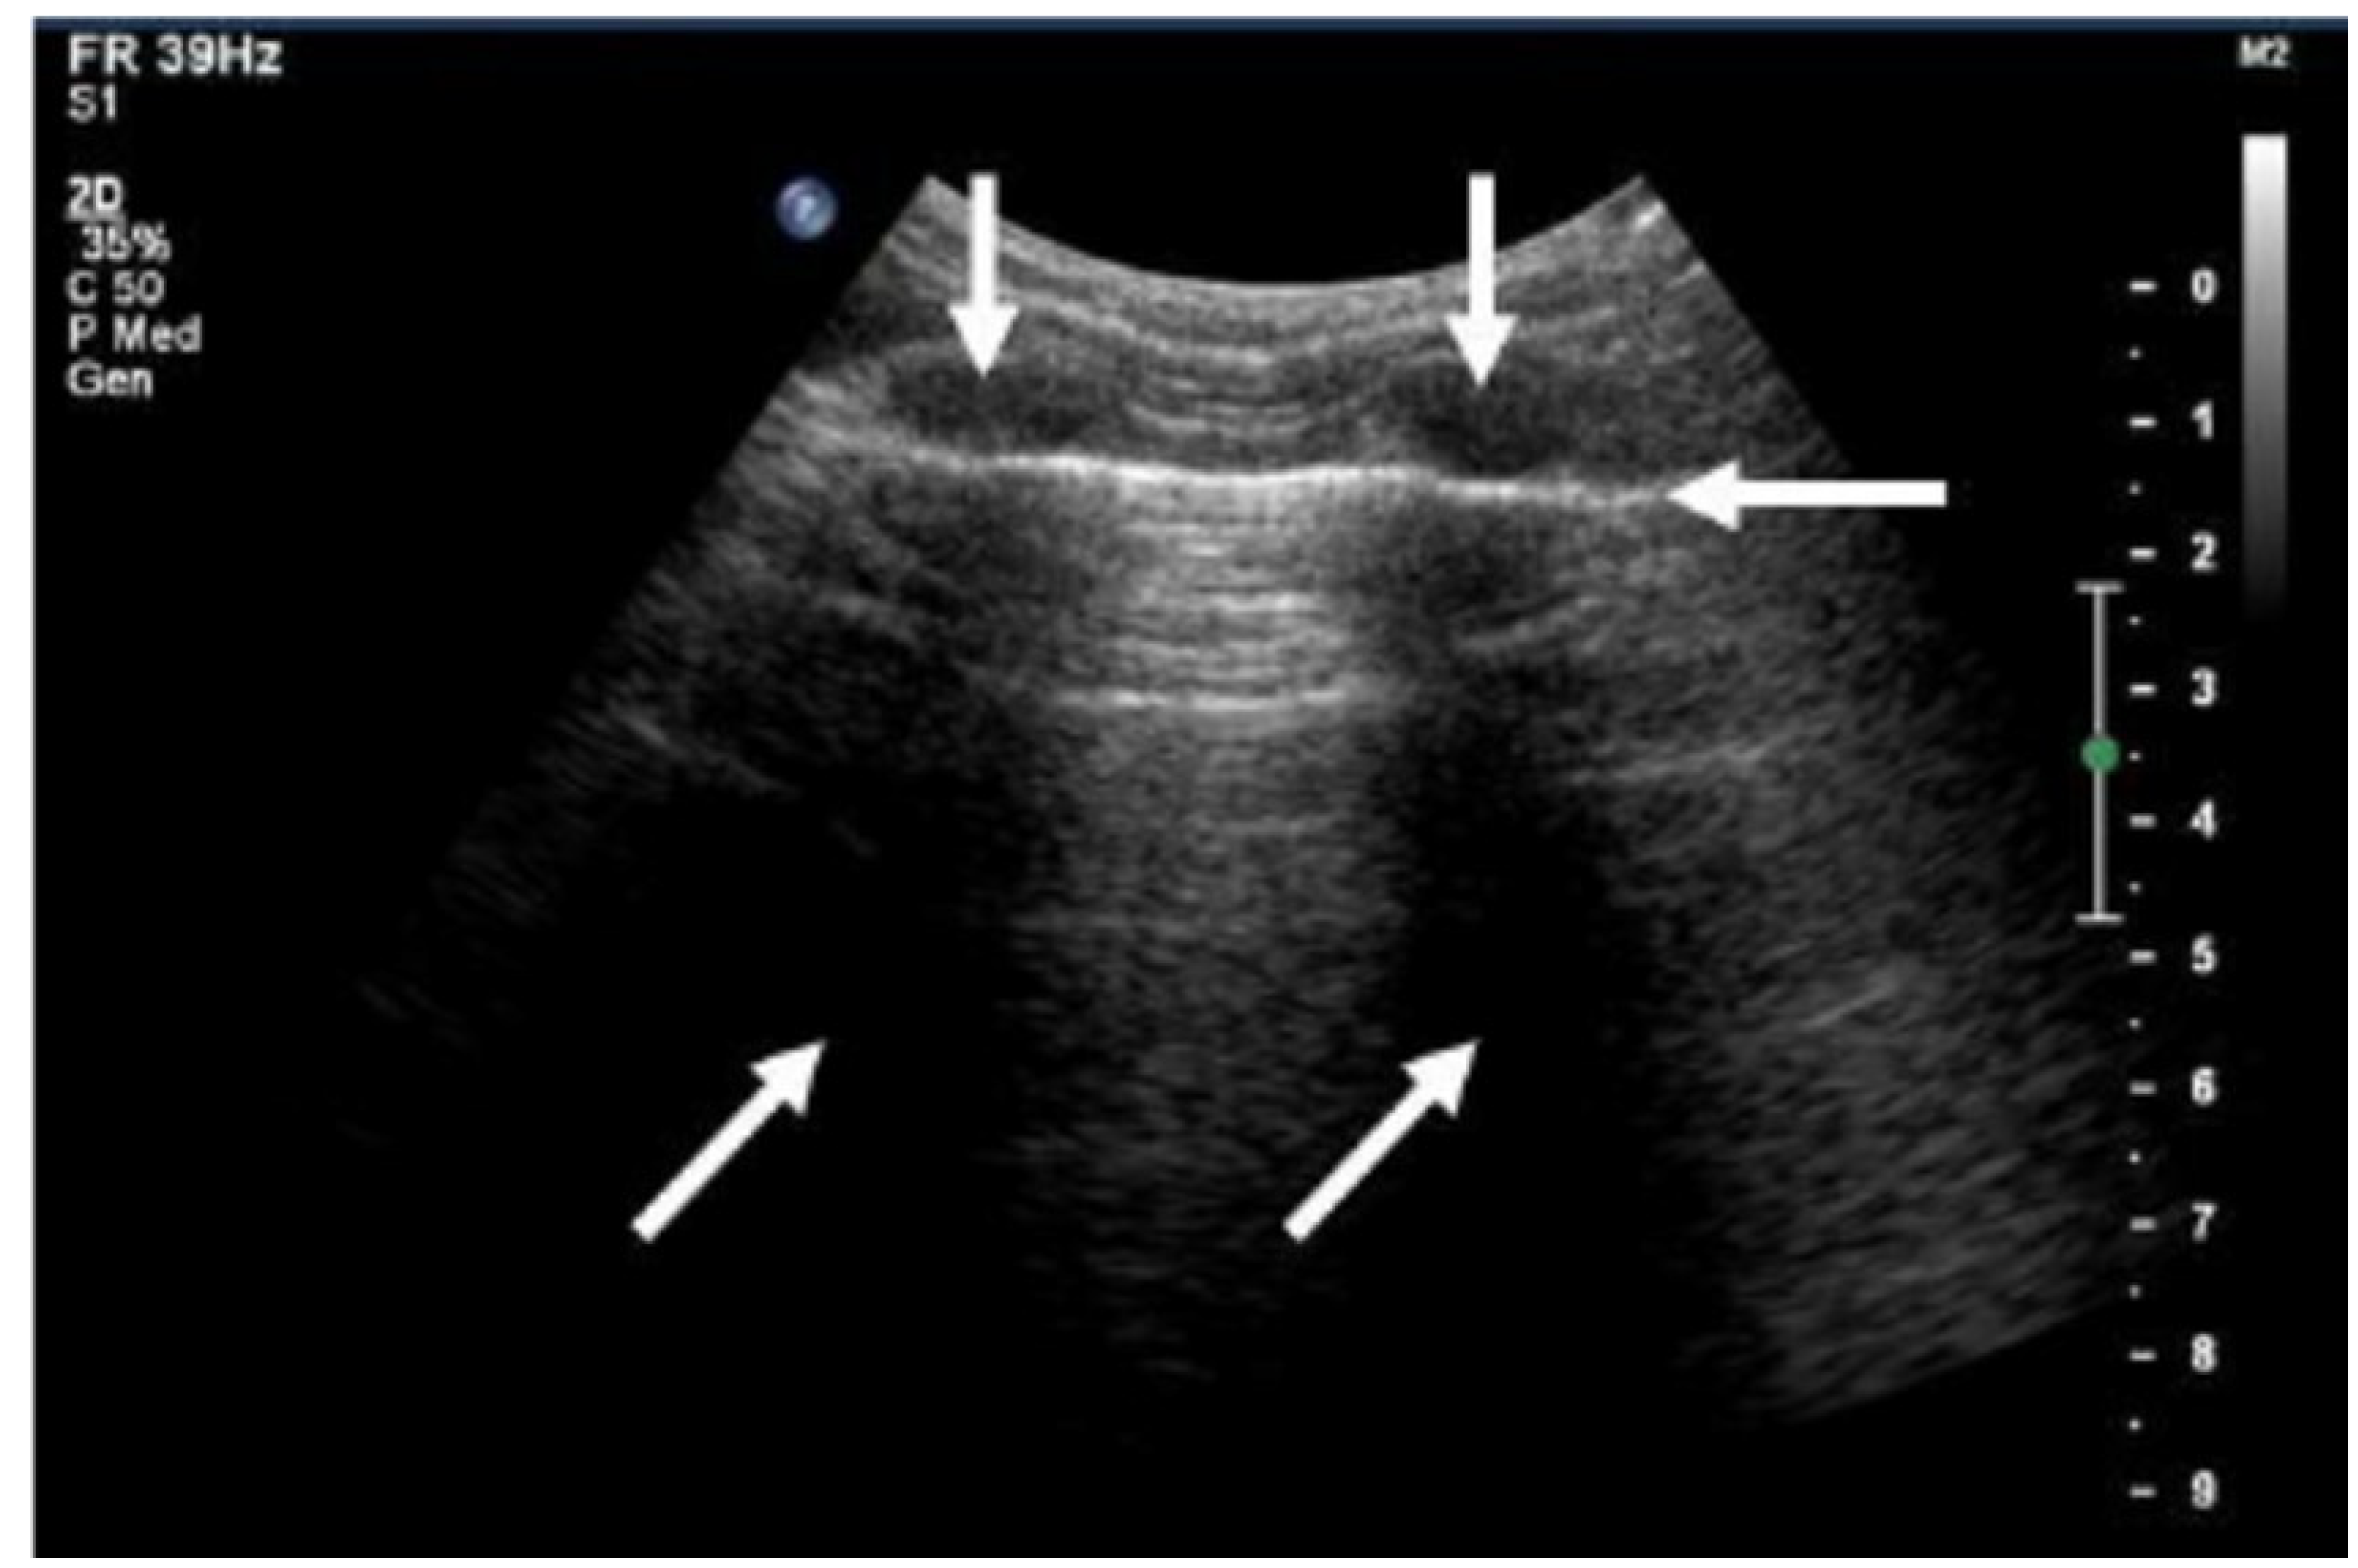

- Rogoza, K.; Kosiak, W. Usefulness of Lung Ultrasound in Diagnosing Causes of Exacerbation in Patients with Chronic Dyspnea. Pneumonol. Alergol. Pol. 2016, 84, 38–46. [Google Scholar] [CrossRef]